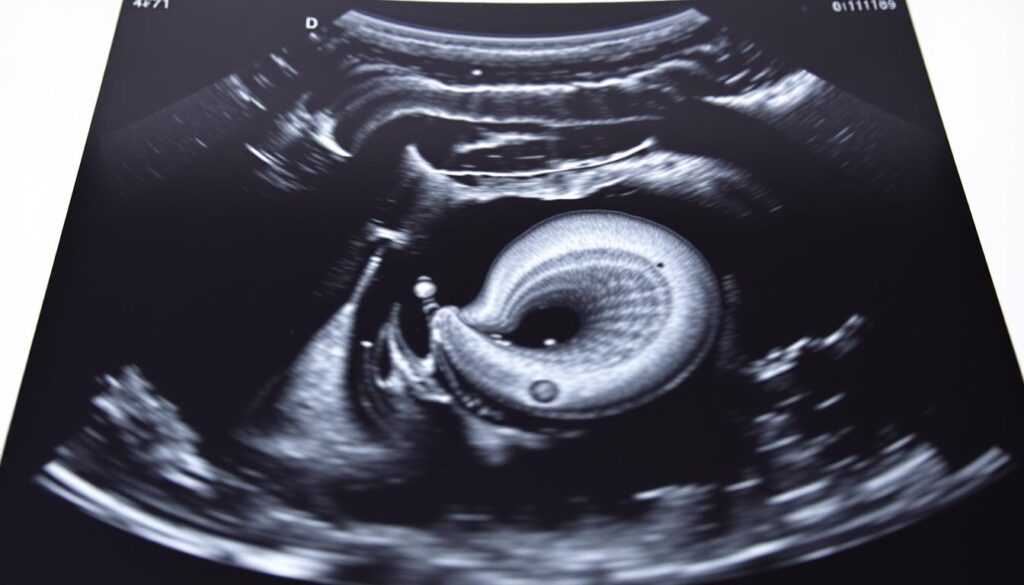

Abdominal aortic aneurysm (AAA) ultrasound is a key tool for finding and tracking aneurysms. At Liv Hospital, we stress the need for precise aorta measurements. This is for effective risk assessment and treatment planning.

An abdominal aortic aneurysm is often found by chance during a physical exam or imaging test. To spot an aneurysm, a doctor checks the aorta’s size. They look at a transverse measurement of 3.0 cm or more as a sign of an aneurysm.

The Role of AAA Ultrasound in Vascular Imaging

AAA ultrasound is key in vascular imaging. It’s very sensitive and specific. We use it to give accurate diagnoses and plans for patients with abdominal aortic aneurysms.

One big plus of AAA ultrasound is its ability to measure aneurysm size accurately. Ultrasound technology gives precise measurements. These are key for figuring out how serious the aneurysm is and what treatment is needed. Also, Doppler ultrasound checks blood flow in the aorta. This gives important info about how the aneurysm affects blood flow.